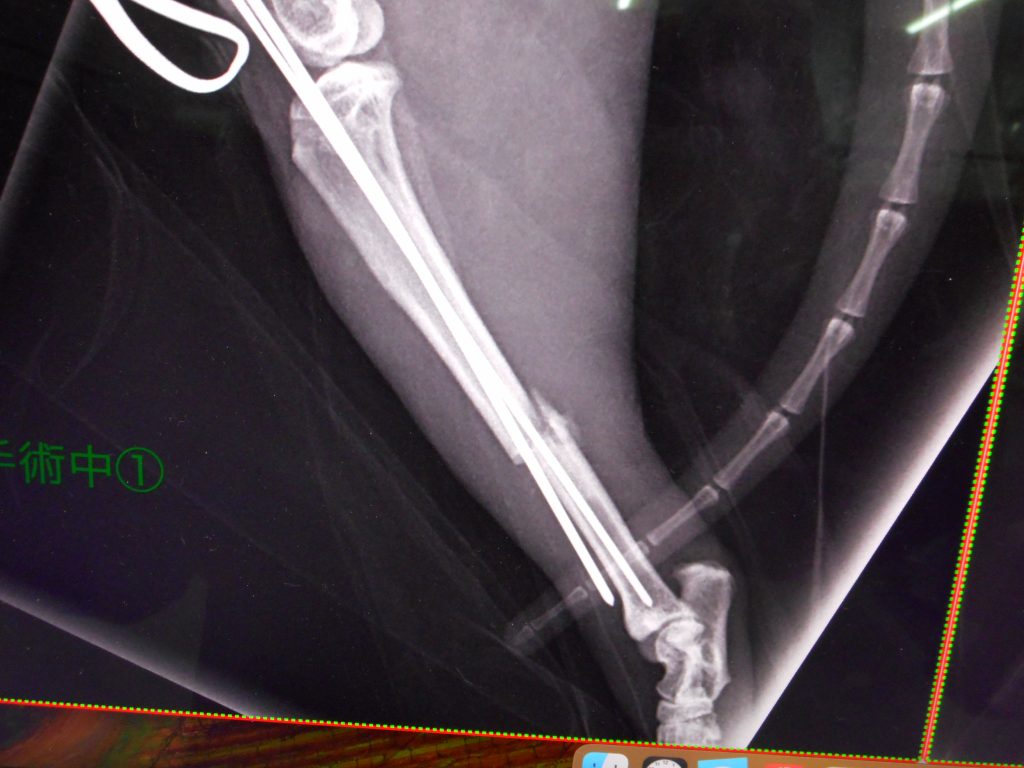

手術です

ピンを入れる手術にしました

ピンがダメな時にはプレートも用意しています

膝からピンを刺入

直径3㎜の骨髄腔にピン

入れるしかないっ

ミス×1

直径1.2㎜と1.5㎜のピン

なかなか入らないのがこの手術のきも

傷を小さくするため膝のみの切開で整復はやや難です

tibia fracture treatment is pinning surgery, we think.

but it is hard to do the surgery.

because of narrow bone marrow cavity and fracture blind surgery